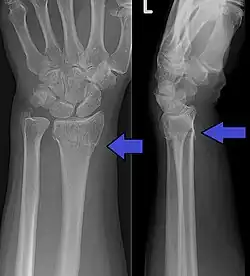

Diagnosis may be evident clinically when the distal radius is deformed, but should be confirmed by X-ray. The differential diagnosis includes scaphoid fractures and wrist dislocations, which can also co-exist with a distal radius fracture. Occasionally, fractures may not be seen on X-rays immediately after the injury. Delayed X-rays, X-ray computed tomography (CT scan), or Magnetic resonance imaging (MRI) can confirm the diagnosis.

Medical imaging

X-ray of the affected wrist is required if a fracture is suspected. Posteroanterior, lateral, and oblique views can be used together to describe the fracture.[5] X-ray of the uninjured wrist should also be taken to determine if any normal anatomic variations exist before surgery.[5]

Distal radius fractures are often associated with distal radial ulnar joint (DRUJ) injuries, and the American Academy of Orthopaedic Surgeons recommends that postreduction lateral wrist X-rays should be obtained in all patients with distal radius fractures in order to preclude DRUJ injuries or dislocations.[11]